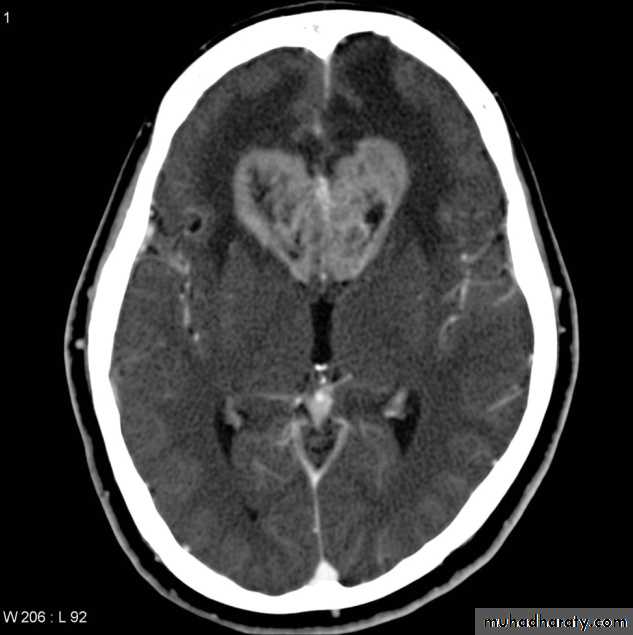

Medullo blastomaAge incidence between 5-15 Y represent about 35-40 %of PFT

Arise from the midline mainly within or from the roof of the 4 TH ventricle fill the fourth ventricle & seeding via the csf so can seen in the distal part of the spinal canal .

CT finding as well circumscribed lesion heterogeneous in density ,have solid & cystic part , with also scattered calcification little surrounded edema , the solid part is enhance

90 % present with obstructive hydrocephalous at the level of the 4Th V. with dilatation of the lateral V. ( body , frontal , temporal & third ventricle )

40 % of child have secondary metastasis at the time of presentation